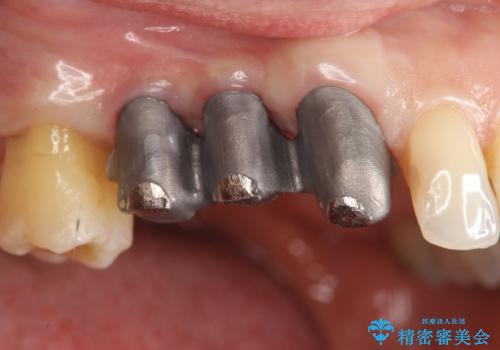

連結補綴について

特定の歯に強く力がかかりまた歯周病により臨床歯根が短くなっているような場合、歯の動揺を抑えるため連結補綴が検討されます。

歯の動揺が続くとより周囲の骨を失い最終的には歯を喪失してしまう可能性が高くなってしまうためです。

今回連結補綴を行うにあたり、歯周病の問題を解決するために再生療法・歯周ポケット除去手術を、またより歯の神経を保存し力に対抗できる環境を整えるために小矯正を行い精度の高いメタルボンドクラウンを製作することができました。